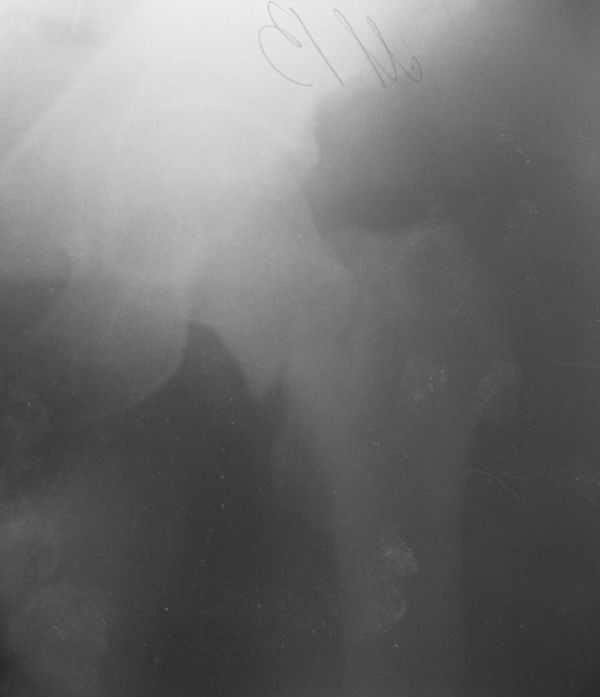

Лечился в ЦРБ. К нам поступил вчера. Имеется оскольчатый перелом диафиза левого бедра, перелом медиального мыщелка, краевой перелом надколенника. У нас, кроме того, выявили перелом шейки бедра. Перелом закрытый, имеется рана в в/3 голени(ниже уровня бугристости б/берцовой кости)без признаков инфицирования.Планируем закрыто фиксировать мыщелок и надколенник винтами, затем закрыто заштифтовать бедро. Вопрос возник по перелому шейки: что предпочесть - длинный PFN или DFN + DHS на шейку?Буду благодарен за ценные советы.С уважением, Станислав Дмитриев.

Заранее приношу извинения за качество снимков. То что есть - либо из ЦРБ, либо сделано в приемном покое, где дежурят рентгенлаборанты различной квалификации. Завтра постараемся сделать снимки всего бедра на длинные кассеты в 2 проекциях. Сейчас больной на скелетном вытяжении. Состояние стабильное.

Я тоже склоняюсь к такой версии.Перелом практически базальный, тип Пауэлс 3 - однозначно нужна угловая стабильность - ни о каких спонгиозных винтах речи нет. Возраст 46 лет, т.е. достаточно молодой - насчет ас. некроза. Накладку DHS вероятно придется ставить монокортикально - штифт получается до малого вертела. Померили расположение имплантов - что называется "стык в стык".